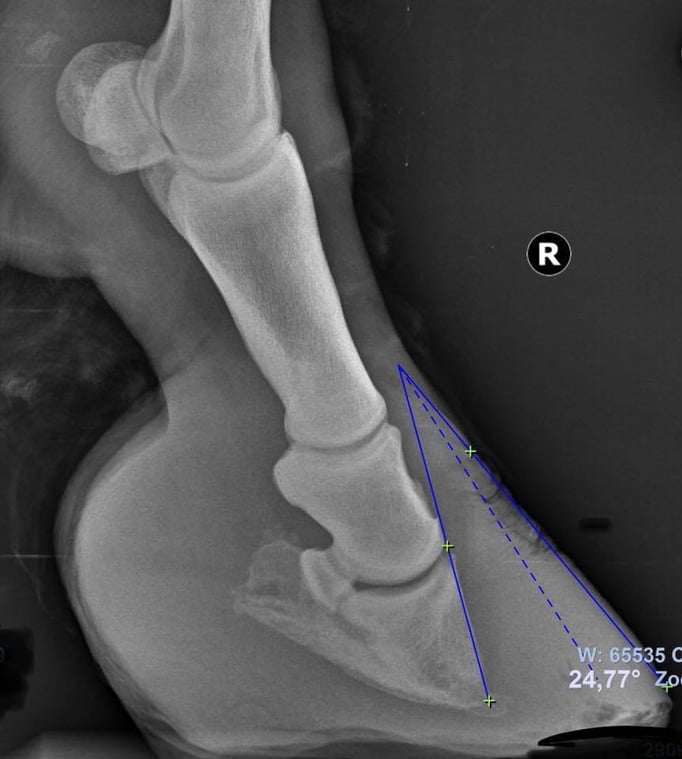

Die Zusammenarbeit von Veterinärtechniker und Tierarzt ist unerlässlich. Röntgenbilder sind absolut notwendig, um die Position des Hufbeines in der Hornkapsel zu erkennen und Sohlen- u. Wandstärke zu beurteilen. Dies ist

maßgebend für die Rehehuf- Korrektur und die Anfertigung des Hufschutzes, einem der Situation angepasster Klebebeschlag. Jeder Rehehuf ist anders, daher gibt es keinen Standardbeschlag. Der Klebebeschlag

• Hufrehe, Haflinger in Oberösterreich

Der Rehe-Huf wurde nach Sichtung der Röntgen Bilder und Rücksprache mit dem Tierarzt korrigiert. Ein reheadaptierter Duplo Beschlag mit Strahlunterstützung wurde angefertigt.